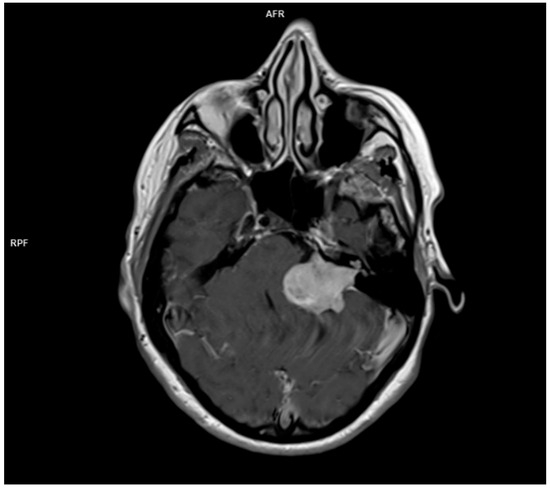

3.1.4. Acoustic Neuroma

- Koos, W.T.; Day, J.D.; Matula, C.; Levy, D.I. Neurotopographic considerations in the microsurgical treatment of small acoustic neurinomas. J. Neurosurg. 1998, 88, 506–512. [Google Scholar] [CrossRef]

- Gentry, L.R.; Jacoby, C.G.; Turski, P.A.; Houston, L.W.; Strother, C.M.; Sackett, J.F. Cerebellopontine angle-petromastoid mass lesions: Comparative study of diagnosis with MR imaging and CT. Radiology 1987, 162, 513–520. [Google Scholar] [CrossRef]

- Deng, F.; Gaillard, F. Vestibular schwannoma. Radiopaedia.org. 2008. Available online: https://radiopaedia.org/articles/vestibular-schwannoma?lang=us (accessed on 29 January 2025).

- Hofmann, E.; Choné, L. Neuroradiologische Bildgebung des Akustikusneurinoms (Vestibularisschwannoms). HNO 2011, 59, 9–15. [Google Scholar] [CrossRef]

- Mulkens, T.H.; Parizel, P.M.; Martin, J.J.; Degryse, H.R.; Van de Heyning, P.H.; Forton, G.E.; De Schepper, A.M. Acoustic schwannoma: MR findings in 84 tumors. Am. J. Roentgenol. 1993, 160, 395–398. [Google Scholar] [CrossRef]